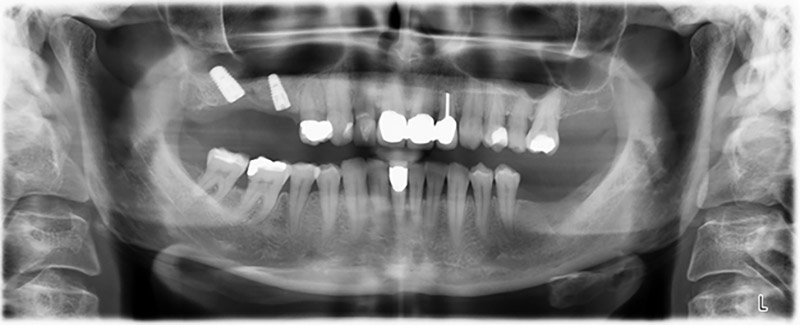

Orthopantomogram

Image 20: Orthopantomogram after treatment